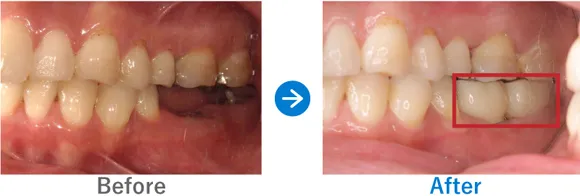

Case3

ブリッジの不具合でインプラントを決意。早めの治療で他の歯を守ることに成功

27年前に治療した右下のブリッジが最近動くようになった。右下7は骨なし

インプラント3本:右下5・6・7、右下5・8抜歯テルプラグ、右下7抜歯ソケットプリザベーション

1,348,600円(内訳:抜歯テルプラグ、抜歯ソケットプリザベーション、インプラント3本(ストローマン)、ガイド、仮歯、セデーション、PMTC、保証20年)

治療結果

抜歯テルプラグ(歯を抜いた穴を保護し回復をうながす処置)と抜歯ソケットプリザベーション(抜歯後の骨吸収を防ぐ処置)を行い、骨の回復と成長を待ってからインプラントを埋入しました。治癒期間に1年以上かかりましたが、無事にインプラントを入れることができました。奥まで噛めるようになり喜んでおられます。

失った歯は右下1本のみだったため、早めのインプラント治療によって他の歯を守ることができました。全顎的にバランスが保てていると思います。